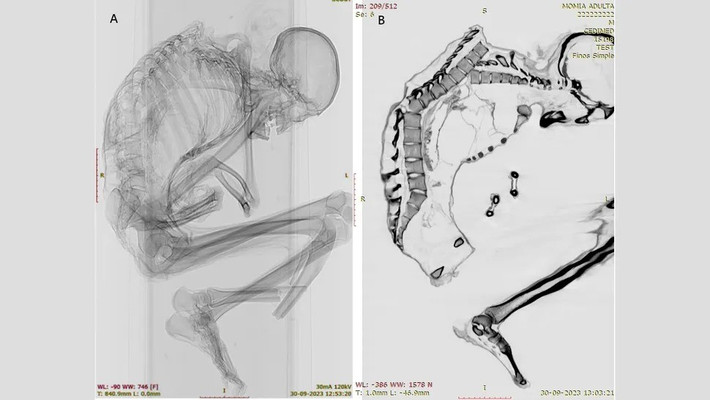

Trên xác ướp có nhiều bằng chứng về chấn thương do lực tác động mạnh cho thấy người đàn ông có thể đã thiệt mạng do đá lở hoặc sập hầm mỏ. Trong nghiên cứu mới công bố, các chuyên gia đã chụp CT và chụp X-quang để giải mã chi tiết những chấn thương nghiêm trọng có thể đã dẫn đến cái chết của người đàn ông trên. Ảnh: Francisco Garrido and Catalina Morales.

Nhiều vết nứt chưa lành được phát hiện trên phần cột sống trên của người đàn ông. Người này cũng bị gãy xương sườn, xương bả vai và xương đòn, cho thấy "một lực tác động mạnh lên một vùng rộng" ở phần lưng trên, tiết lộ rằng "phần ngực trên bên trái của ông chịu lực tác động chính". Điều này đã dẫn tới một số đốt sống bị lệch và làm xẹp lồng ngực. Ảnh: geologyin.com.

Ngoài ra, các nhà nghiên cứu đã xác định được một vết nứt ở đốt sống gần gốc cột sống của thợ mỏ, có khả năng là hậu quả của chấn thương ban đầu ở phần lưng trên. Cả chấn thương cột sống trên và dưới đều "thường liên quan đến tổn thương tủy sống nghiêm trọng và tỷ lệ tử vong cao. Ảnh: pueblodirect.com.

Nhóm nghiên cứu không phát hiện thấy thương tích nào ở hộp sọ, cổ hoặc cánh tay của người đàn ông. Điều này cho thấy vụ tai nạn xảy ra khi người thợ mỏ đang ở tư thế cúi đầu. Lúc xảy ra tai nạn lao động, có thể ông đang tập trung khai thác ngọc lam hoặc có lẽ đang cố gắng bảo vệ phần đầu bằng hai tay khi một tảng đá nặng rơi từ trên cao rơi xuống. Ảnh: pueblodirect.com.